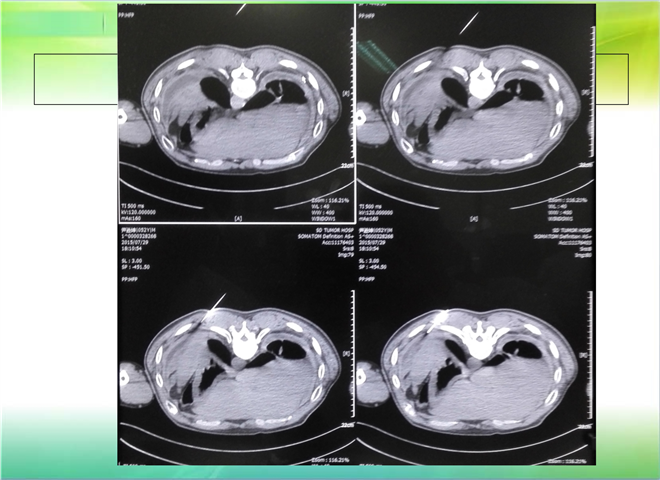

CT引导下穿刺活检术